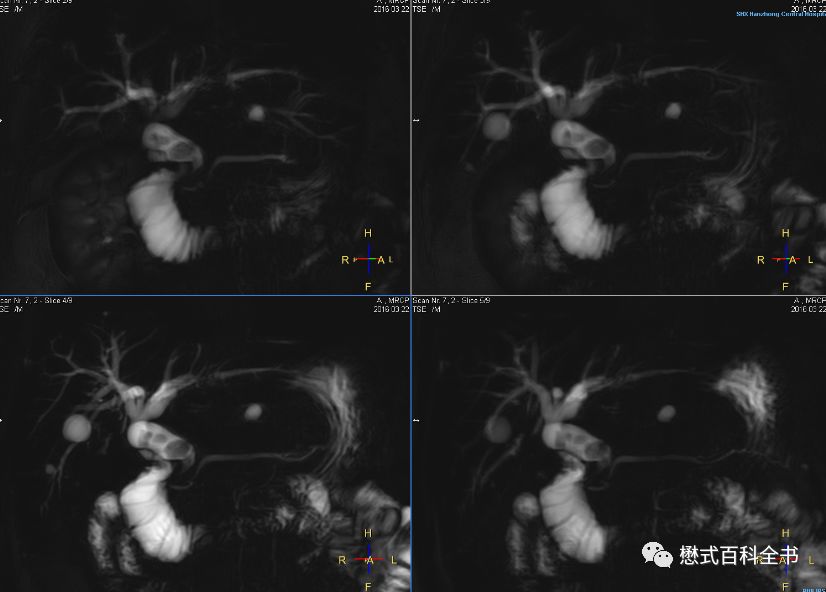

图22:2D MRCP扫描

如图,2D单激发MRCP扫描。一次激发采集一层或者多层。

2D MRCP优点是:扫描速度快。一次激发采集1层或者多层,直接出图像,能够很好的显示结石的充盈缺损。

缺点是:信噪比比3D的低,一次扫描出1~几层,单层层厚厚,有部分容积效应。

所以,理论上为了保证好的诊断效果,我们推荐3D MRCP和2D ssh MRCP都要扫描。当然,3D MRCP扫描完,一定要看原始薄层图像,有经验的诊断医生不可能只看MIP图去诊断。